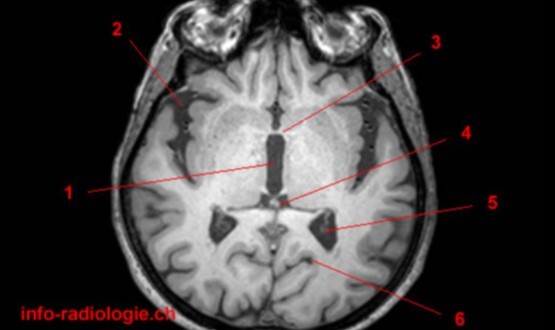

1

Q

Label 1-5

A

1. Rt putamen

2. Rt globus pallidus

3. Rt Caudate nucleus

4. Lt Insula

5. Choroid plexus of left lateral ventricle